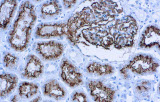

L'immunoistochimica (IHC) rimane un metodo centrale in ematopatologia perché fenotipi diagnostici significativi possono essere risolti direttamente nell'architettura tissutale, utilizzando marcatori di lignaggio, differenziazione e proliferazione definiti da anticorpi. Per qualsiasi anticorpo CE-IVD o anticorpo IHC destinato a flussi di lavoro di ricerca clinica/diagnostica, la pratica basata sull'evidenza enfatizza la validazione analitica e il controllo delle variabili preanalitiche e analitiche per garantire risultati accurati e riproducibili.

- Pannelli orientati alle entità per neoplasie linfoidi:

- Linfoma follicolare: tipici pattern di co-espressione (es. CD10 con BCL2 aberrante).